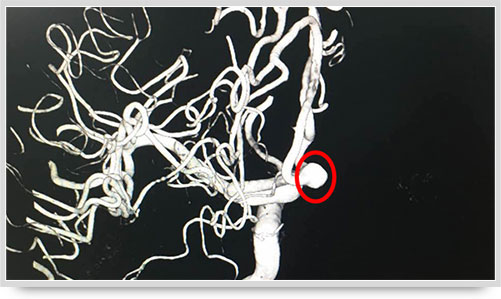

之前,另一位61岁的李姓脑出血患者,康复治疗半个月后复查,也接受了全脑血管造影术,术中显示大脑前动脉A1段动脉瘤(不同维度显影,红圈内为动脉瘤瘤体)。像这样的病人,必须进一步进行手术治疗,及早清除动脉瘤,避免因瘤体破裂造成再次出血危及生命。